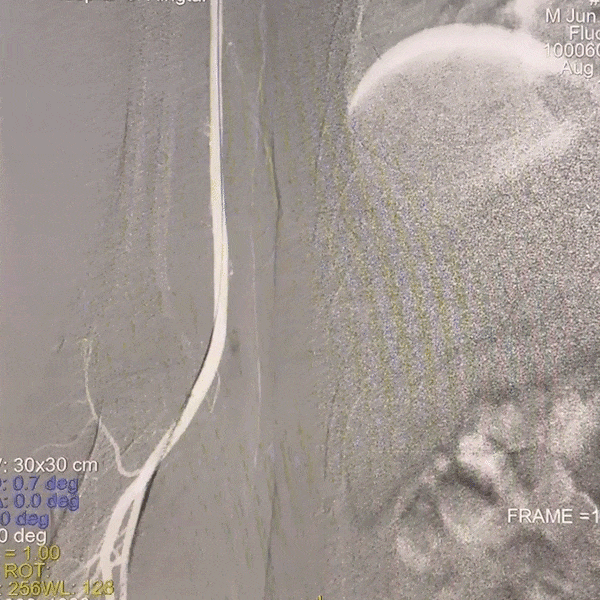

通路建立:经桡造影显示Ⅲ型弓,病变为右侧颈内动脉C4段动脉瘤,患者桡动脉纤细不适合经桡治疗,故选择经股动脉应用赛诺神畅APEX TRA GC™5F-130 SIM2导引导管超选右颈,同轴长鞘建立通路。

动脉长鞘怎么置入一技之“长”丨经桡及经股困难入路应用赛诺神畅APEX TRA GC™导引导管建立通路病例合集_https://www.jmylbn.com_新闻资讯_第20张

Ⅲ型弓

动脉长鞘怎么置入一技之“长”丨经桡及经股困难入路应用赛诺神畅APEX TRA GC™导引导管建立通路病例合集_https://www.jmylbn.com_新闻资讯_第21张

SIM2导管成袢

动脉长鞘怎么置入一技之“长”丨经桡及经股困难入路应用赛诺神畅APEX TRA GC™导引导管建立通路病例合集_https://www.jmylbn.com_新闻资讯_第22张

超选入无名动脉

跟进长鞘至右侧颈内动脉。